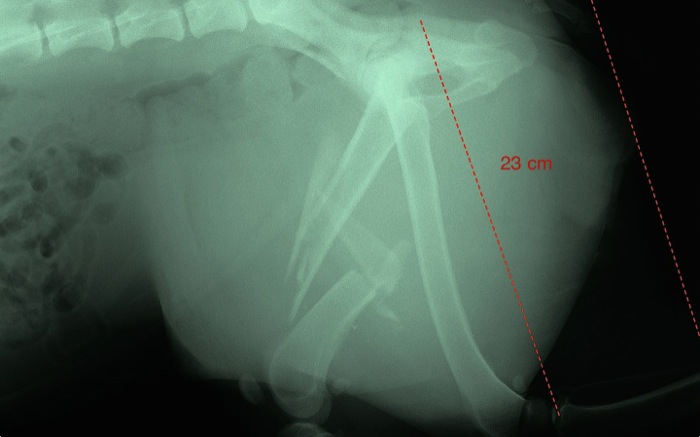

| Pruebas | La radiografía pone de manifiesto la presencia de grandes esquirlas que dejan grietas muy amplias en el fragmento proximal a 4 centímetros del cuello femoral. |

El fémur tiene una gran longitud pero las esquirlas dejan un área de trabajo bastante limitada sobre todo en la parte proximal desde donde parte un gran fragmento.

Se corta casi un centímetro de las dos puntas del fragmento proximal y se eliminan por ser las responsables de estar ante una fractura abierta, quizá estar contaminadas y tener un final tremendamente cortante. Se pierde por ello un centímetro de la longitud del fémur.